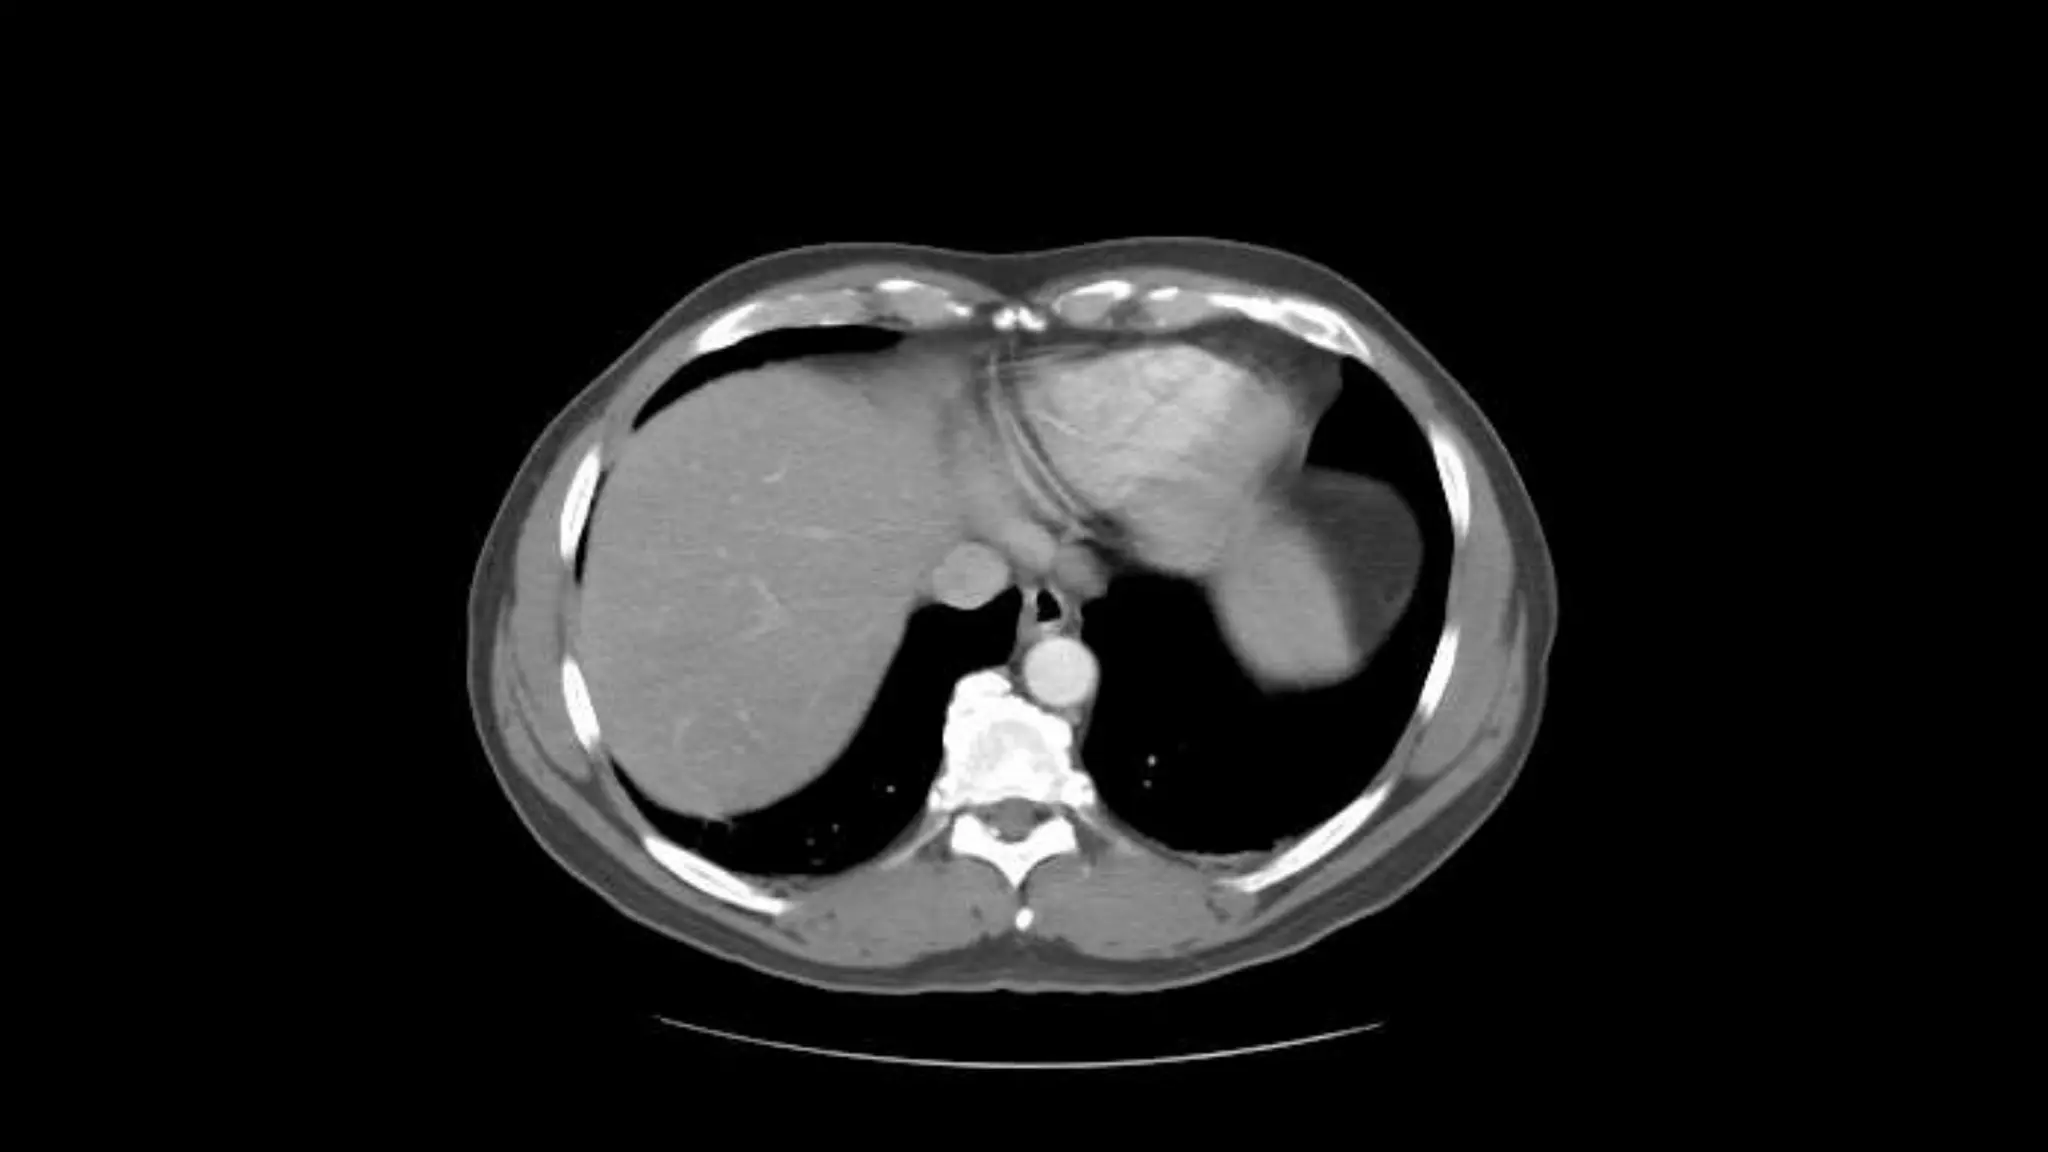

 In this sequence of images, we will label the abdominal vasculature.

The CT images are 5mm slices with soft tissue window settings. IV

and oral contrast have been administered which causes the vessels

and GI tract to appear hyperdense (white). Some images will contain

labels to assist with tracking the vessels.

Studying the CTimage  In this sequence of images, we will label the abdominal vasculature. The CT images are 5mm slices with soft tissue window settings. IV and oral contrast have been administered which causes the vessels and GI tract to appear hyperdense (white). Some images will contain labels to assist with tracking the vessels.  IMAGES ARE VIEWED AS LOOKING FROM THE FEET RIGHT LEFT